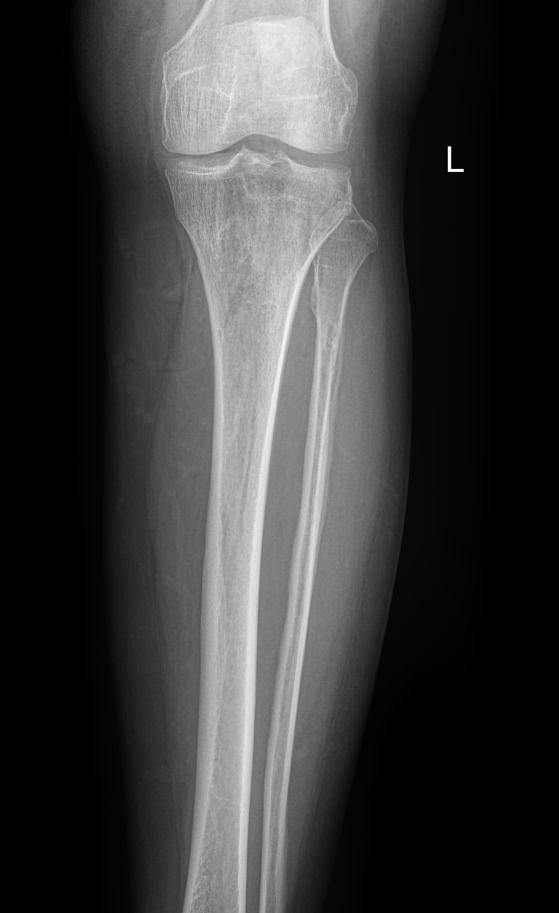

В области голени располагаются 2 кости ― большая и малая берцовые. Разные по толщине, они, тем не менее, составляют крепкую конструкцию, позволяющую человеку ходить и бегать, нести вес тела и дополнительный груз. Повреждение и травмы голени, а также прилежащих суставов, коленного и голеностопного, резко уменьшает мобильность человека. Хронические процессы, начинаясь незаметно, постепенно приводят к тому же.

Рентген является простым, доступным, высокоинформативным и безболезненным видом диагностики патологий костной ткани, в том числе ― костей голени. А современная цифровая аппаратура позволяет выполнять снимки настолько часто, насколько этого требует заболевание, не превышая допустимую дозу облучения.

На снимке рентгенолог последовательно просматривает все образования голени и описывает их изменения:

• Новообразования: местоположения, затрагивают ли костную ткань;

• Диафизы и эпифизы костей: наличие перелома, его смещения, костной мозоли, их месторасположение и соответствие срокам травмы;

• Костная ткань: очаги разрежения, уплотнения, размягчения, склерозирования и других изменений, в том числе послеоперационных;

• Надкостница: истончение, обызвествление;

• Входящий в снимок сустав: есть ли изменения, типичные для травмы или воспаления;

• Мягкие ткани: есть ли отек и инородные тела.